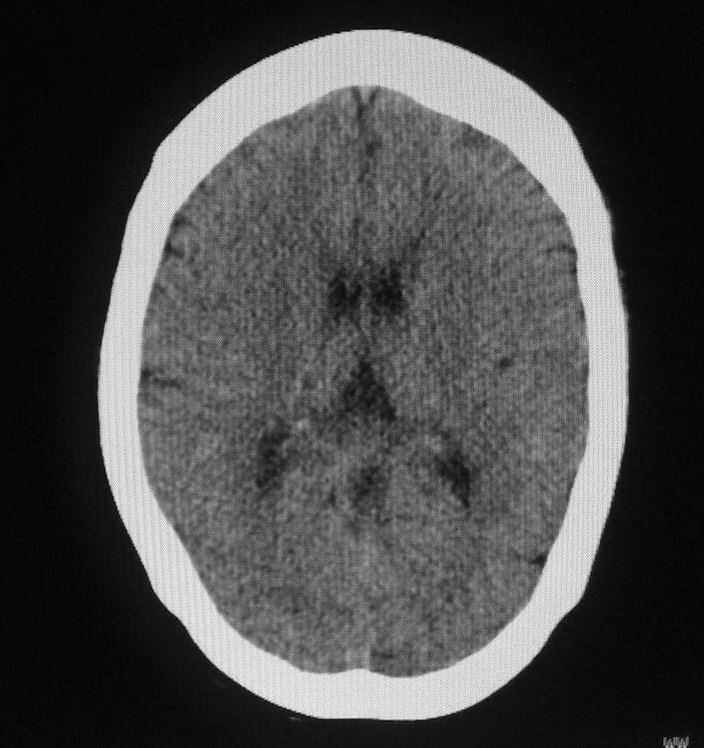

女,46岁,走路有时向一侧偏斜。是小脑萎缩吗?

小脑脑沟增多加深      为小脑萎缩引起的共济失调

小脑脑沟多于四条即为增多,又见加深,所以支持小脑萎缩。

从图像上看的确有轻度小脑萎缩征象,但患者才46岁,有外伤史吗?

小脑萎缩可能性大,建议mri检查。

小脑轻度萎缩